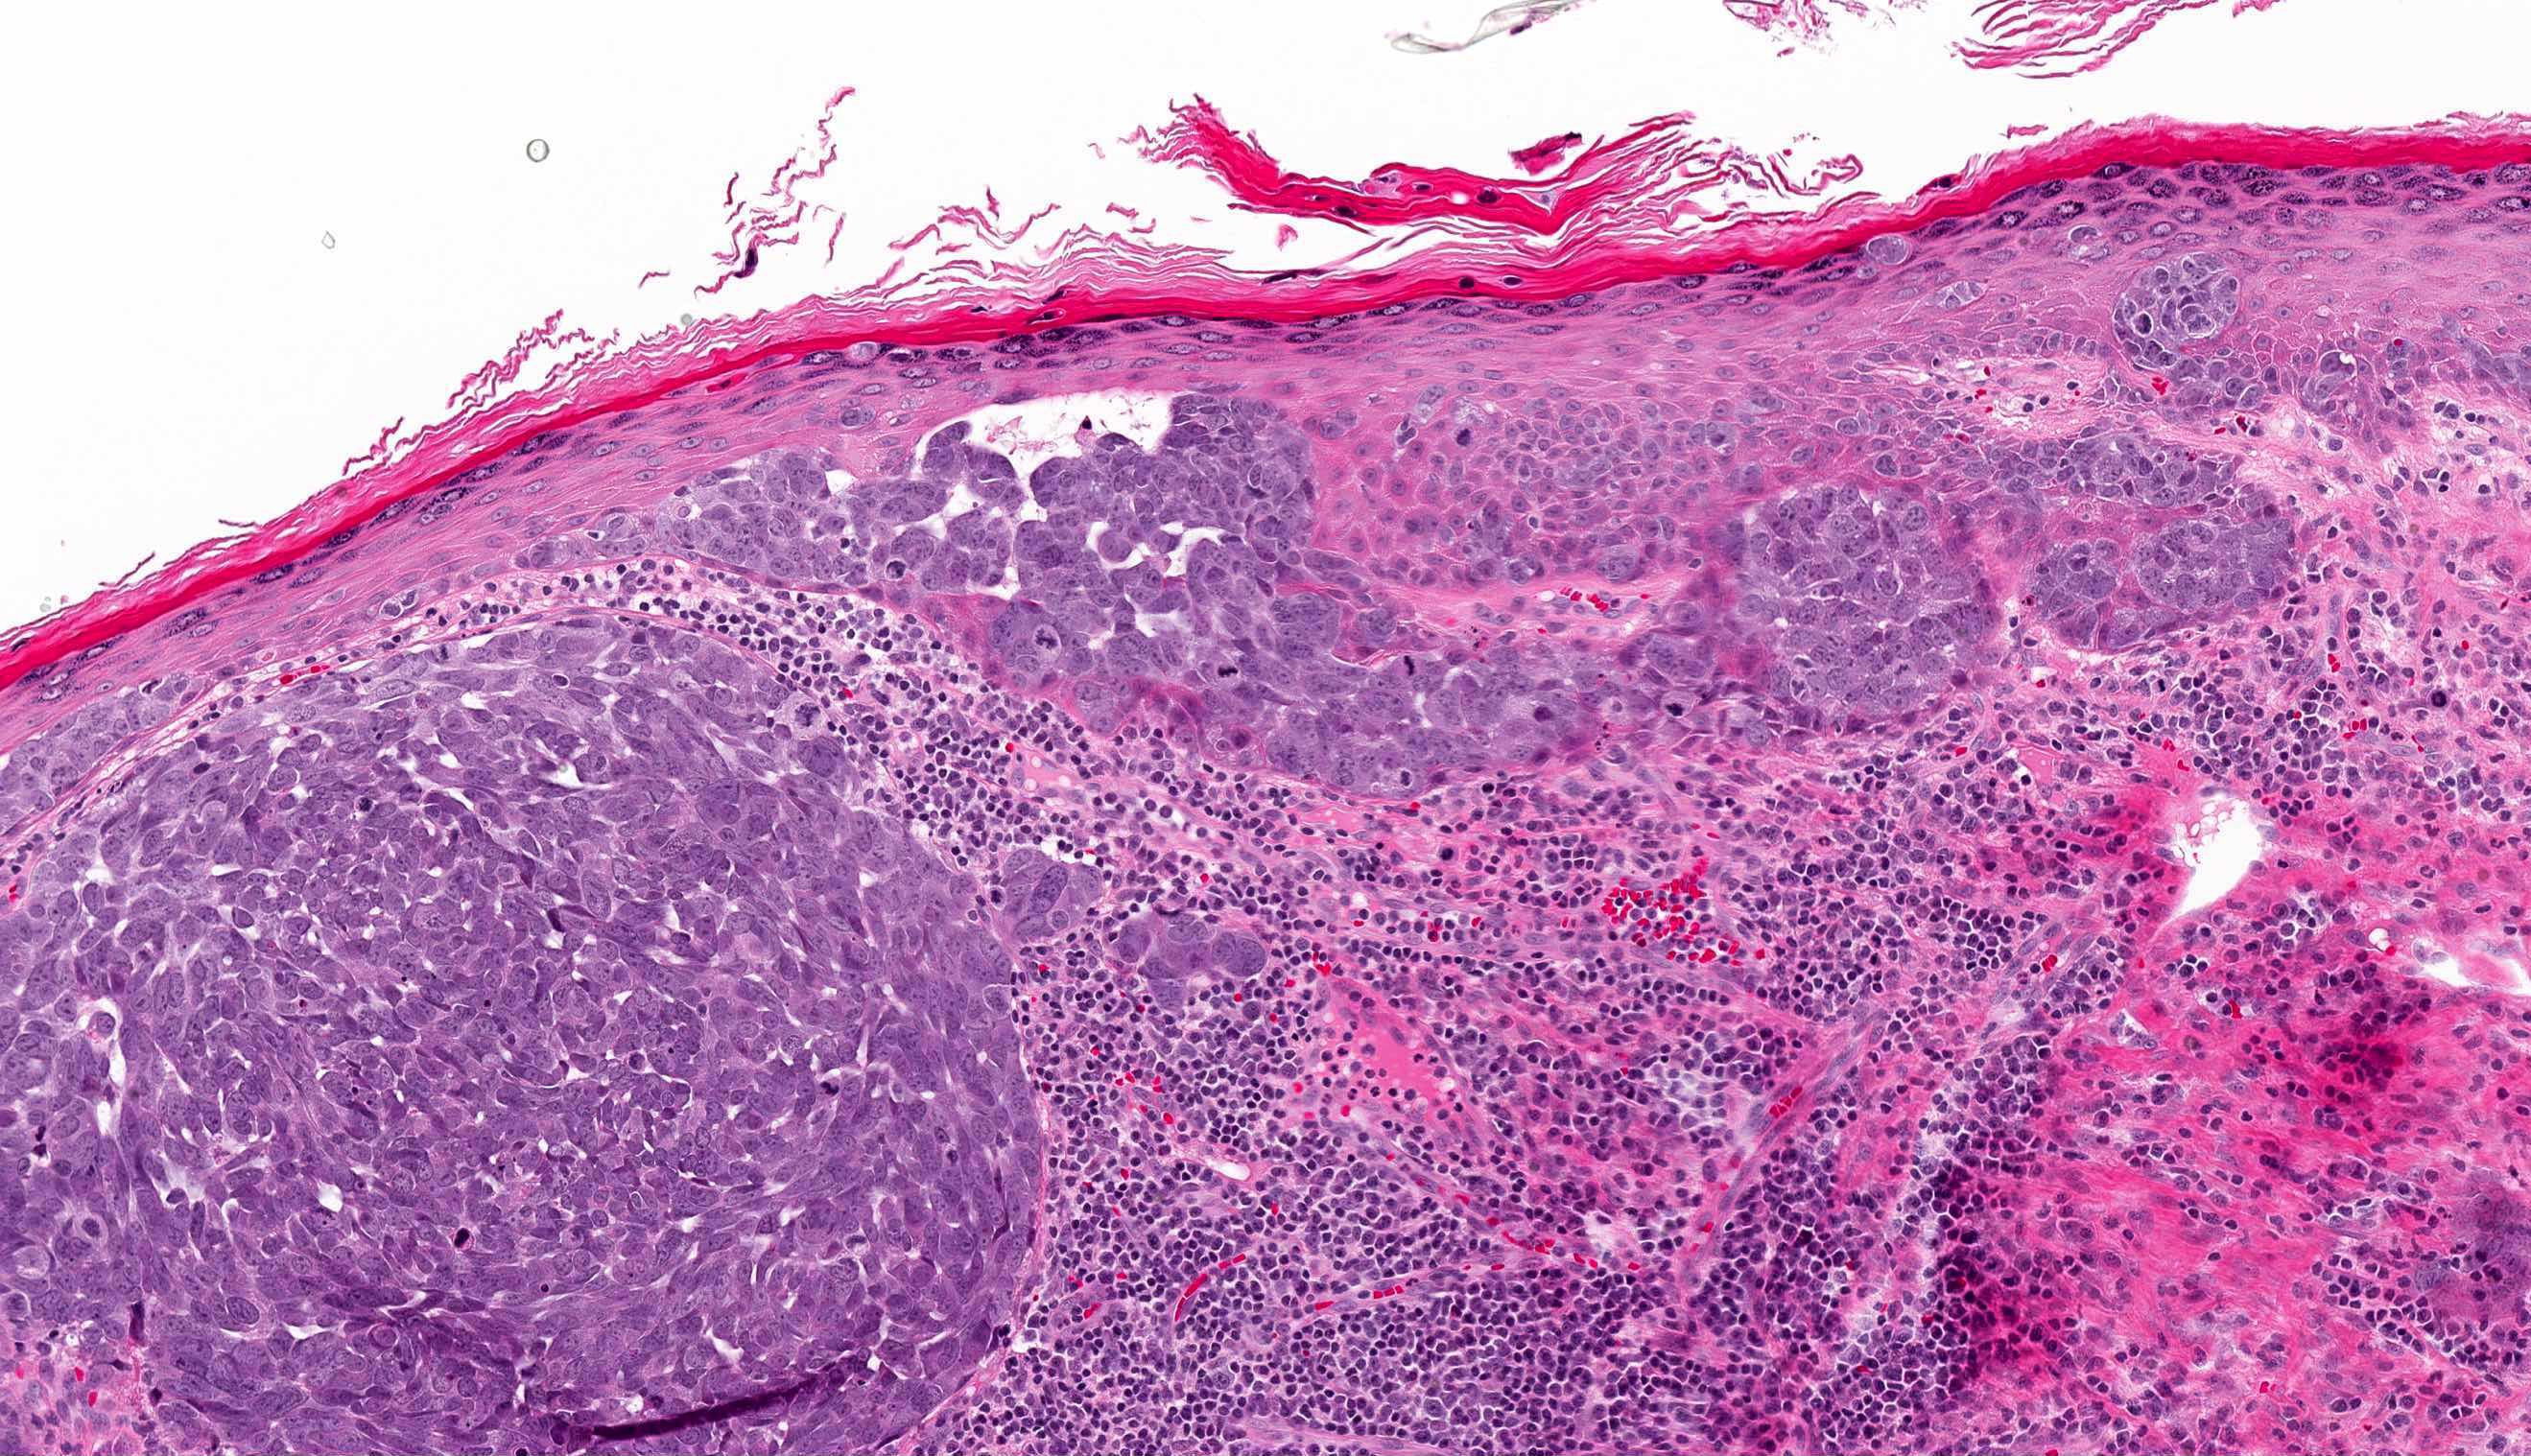

- Expansile, nodular or diffusely infiltrative tumor within the dermis, variably in subcutis

- Variable mixture of nodules, sheets, nests and trabeculae of neoplastic cells

- Intraepidermal tumor (or component) is occasionally present

- Generally, small round blue cell tumor with high N:C ratio, round / oval nuclei, finely dispersed chromatin (salt and pepper), indistinct nucleoli and scant cytoplasm

- Minority of cases feature neuroendocrine and other elements (combined Merkel cell carcinoma) such as divergent differentiation (e.g. squamous, sarcomatoid) or intimate association with other cutaneous neoplasms (most commonly in situ or invasive squamous cell carcinoma)